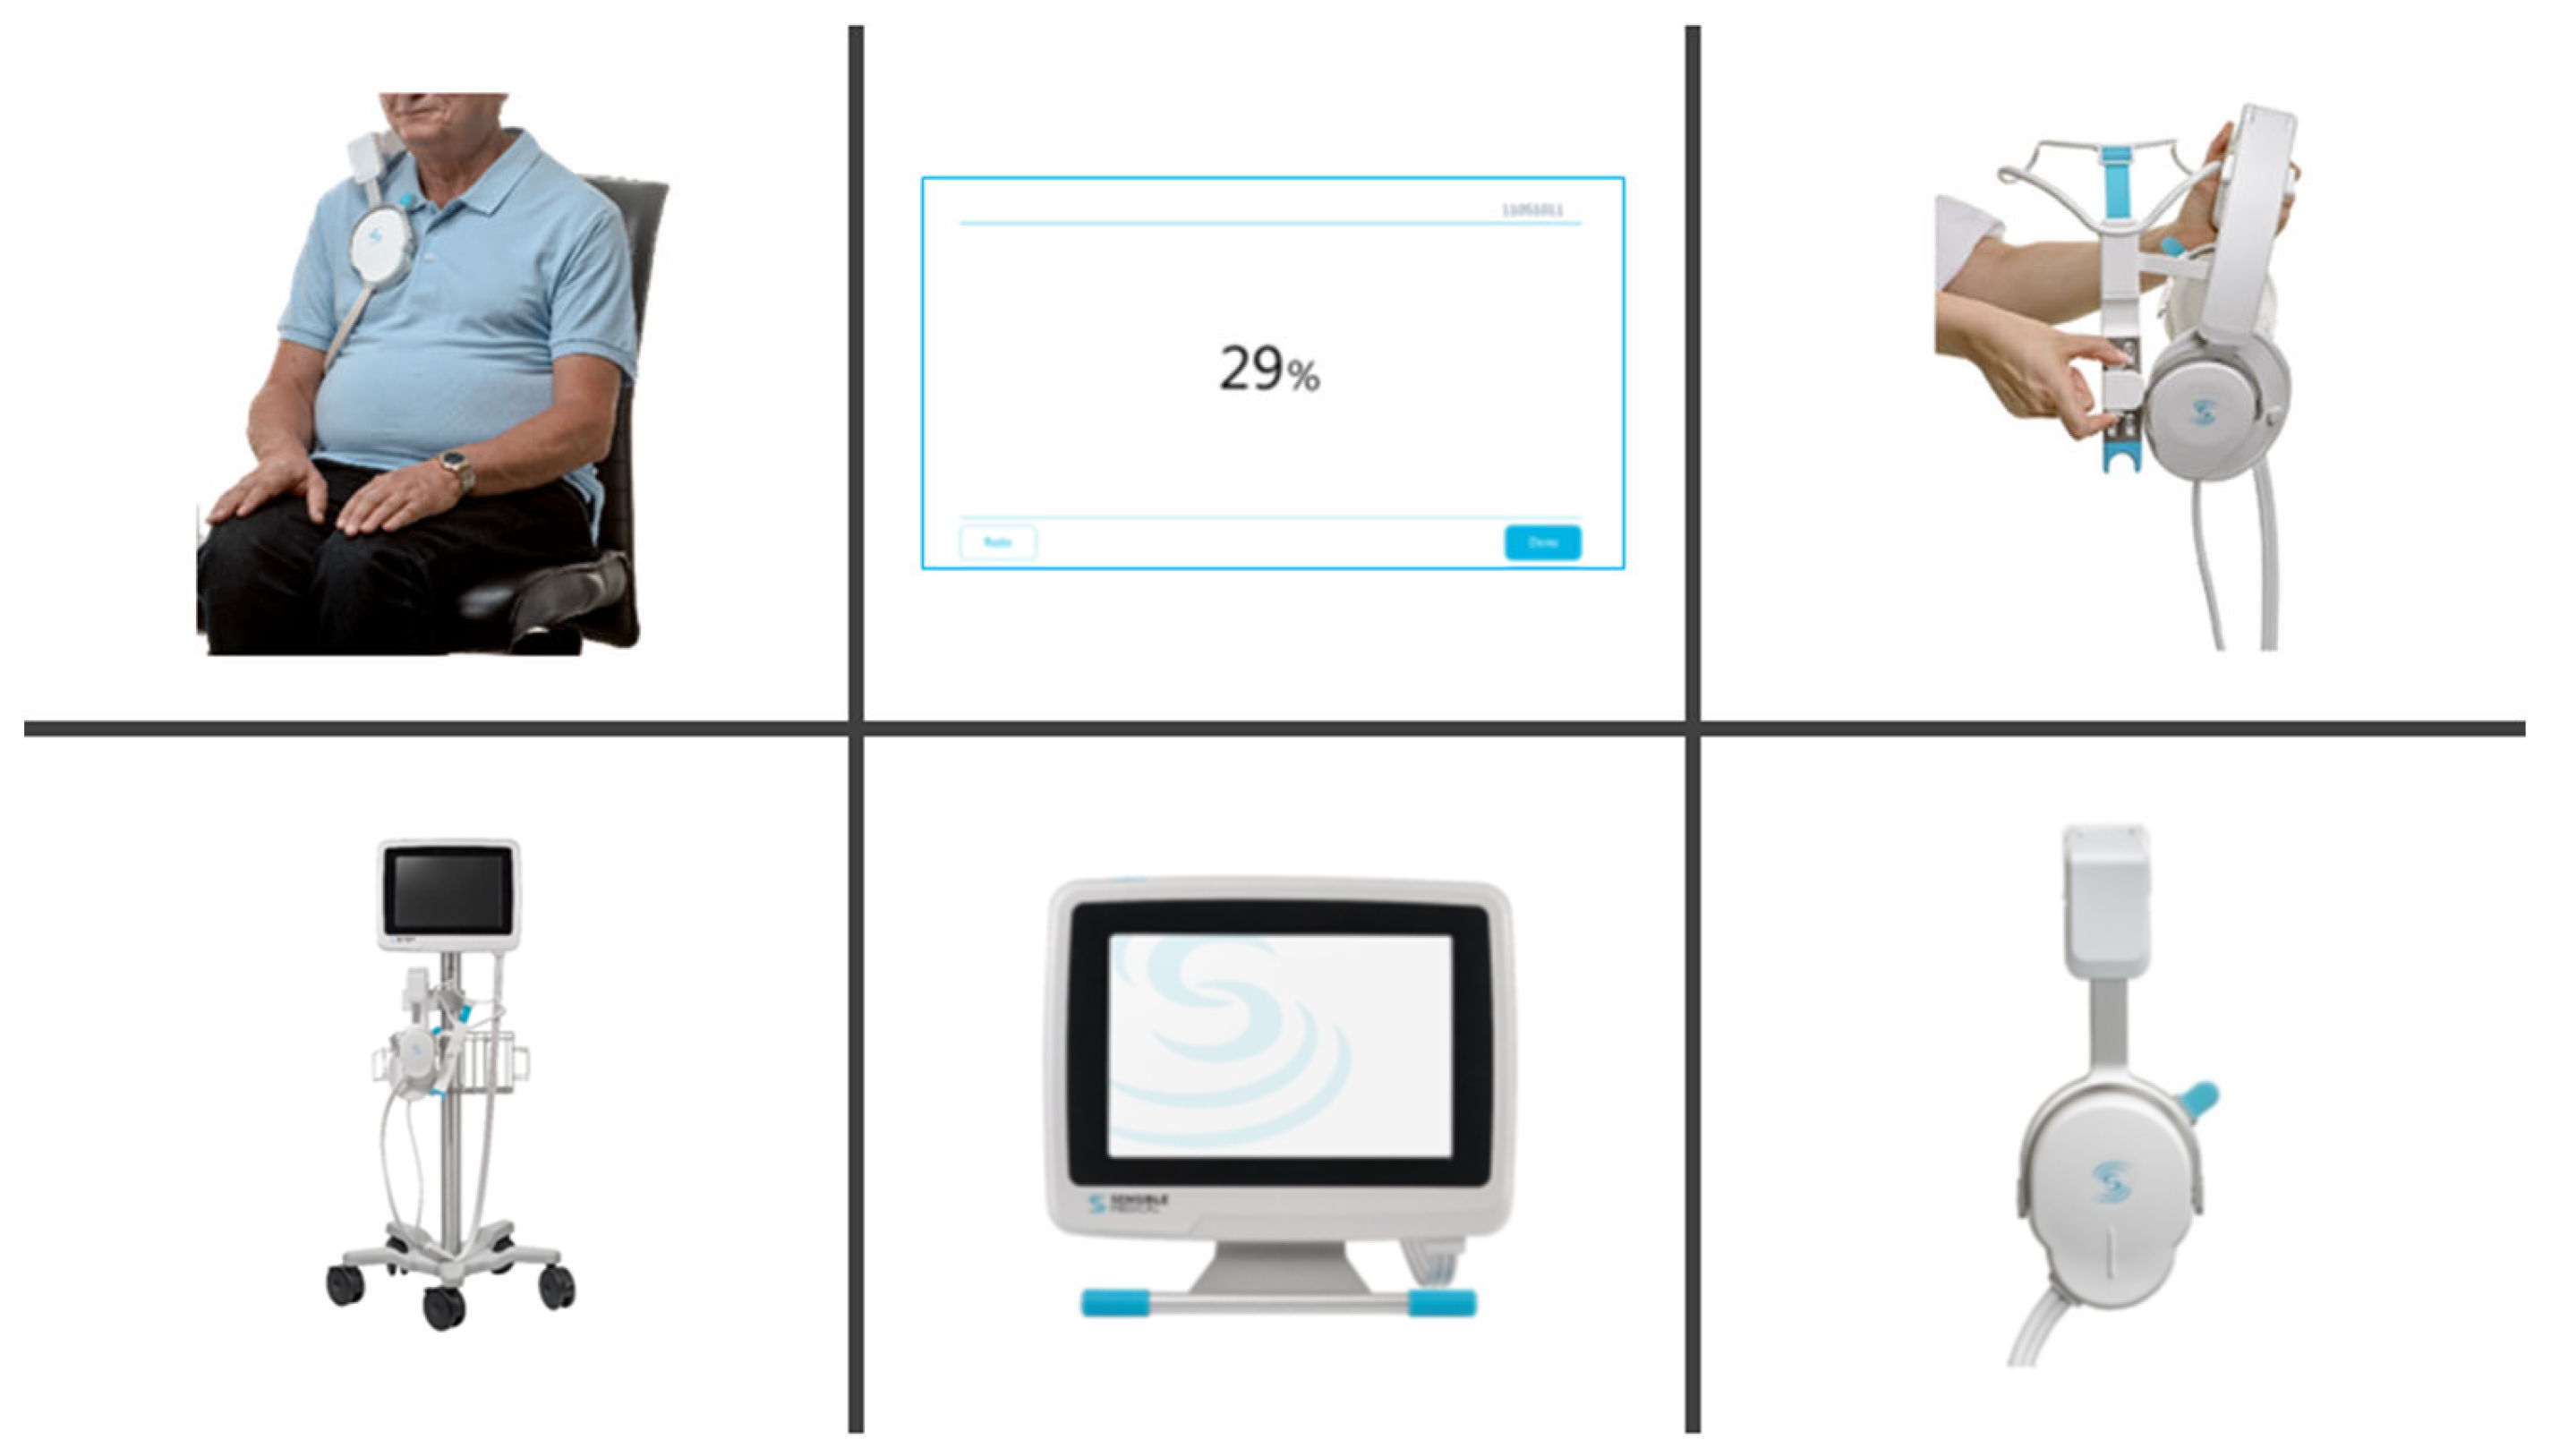

2.3. ReDS Measurement